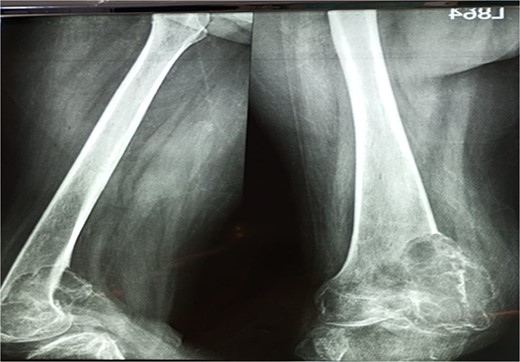

The examination revealed severe difficulty in walking independently. A scar mark measuring 3 cm at the left distal thigh was appreciated, along with a fixed flexion knee deformity of the left knee around 40 degrees. The swelling was firm, non-mobile, and tender on palpation. There was no neurovascular deficit. The obstetric evaluation confirmed the normal fetus status (Fig. 3).